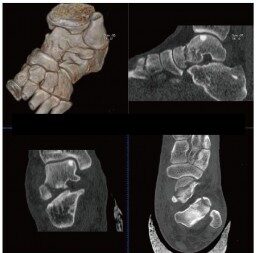

CT検査とはレントゲン(X線)を利用し身体の写真を撮影する検査です。

マルチスライスCT撮影装置

当院では、ドイツ・シーメンス社製マルチスライスCTを導入いたしました。

この装置は高速で回転し、短い時間で検査が可能な最先端マルチスライスCTで、従来の装置と比較して息を止める時間が短縮されます。また細かい情報を得ることができ、脳や腹部の血管や骨などの3D画像(立体再構成画像)を高精細に描出可能です。さらに、X線の被ばくも従来のCT装置に比べ低減されています。

頭だけではなく、全身のCTを撮ることが出来ます。